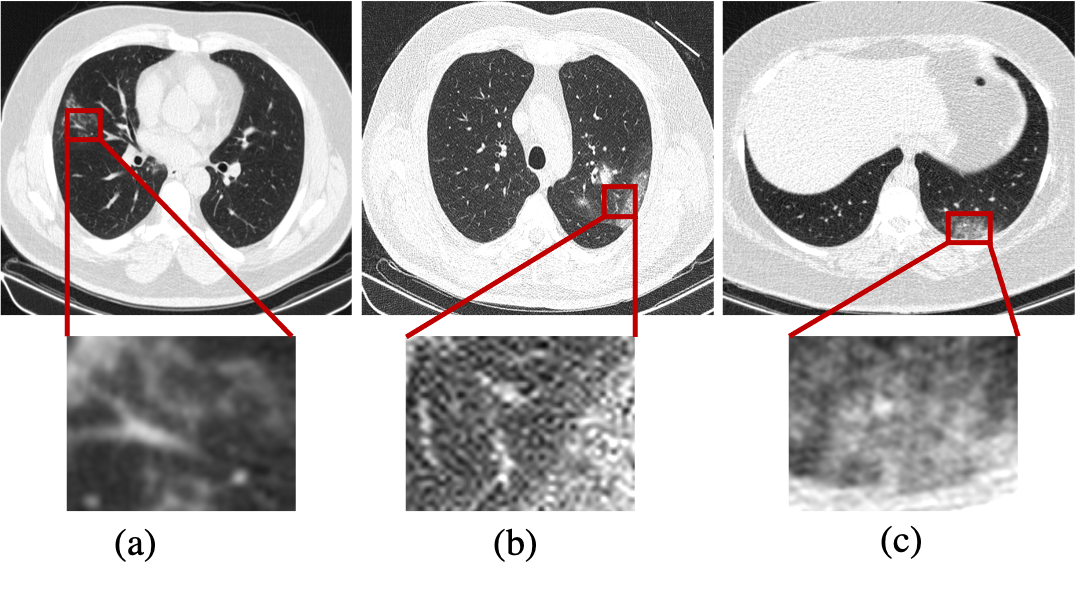

There has been considerable attention on CT imaging as the most useful imaging modality for representing COVID-19 infections. A study [25] on 515151 patients with positive nucleic acid testing reported that only 3.93.93.9% of patients were misdiagnosed based on their chest CT images. Fig. 3 shows common CT patterns in COVID-19 patients, where the most prevalent are “Ground Glass Opacities (GGOs)” and “Consolidations”. GGO is a hazy transparent opacity that does not conceal lung vessels and bronchial areas [26]. In a consolidation pattern, the air in the alveoli and peripheral bronchioles is replaced by fluid such as pus, water, blood, or an inflammatory material, obscuring the underlying distal airways and vascular margins [26]. In a research study on 645645645 confirmed COVID-19 patients, 888888% of patients showed either pure GGOs or consolidation or both [27]. The appearance of pure GGO is more common in the early stage of the disease, while the appearance of GGOs with consolidations is more frequently seen in the progressive stage [28]. Another common CT pattern associated with COVID-19 is the so-called “Crazy Paving” referring to thickened interlobular septa and intralobular interstitium superimposed on GGOs [26]. The crazy paving pattern is more commonly seen in the progressive stage of the disease [28]. The appearance of the crazy paving/consolidation patterns as a sign of disease progression/severity can help radiologists evaluate the disease stage. Interlobular septal thickening, air bronchogram, and vascular enlargement are other CT findings in COVID-19 patients [28].

COVID-19 CT Scans & CXR Datasets: To assure model generalization for clinical use, it is beneficial to train SP/DL models based on a diverse set of dataset acquired from different scanners, different health centers covering a wide range of patients. Table III provides an overview of the available CT imaging datasets along with their COVID-19 related information. CT images represent different resolutions and contrasts depending on the type of scanner, image acquisition approach, and the thickness of the slices. It is, therefore, necessary to make CT images consistent before feeding them into the processing and learning models. For a list of available CT imaging datasets along with their COVID-19 related information please refer to Reference [29]. Given the heterogeneity of the data source, available data collections comprehend a wide sort of equipment, images characteristics and diagnosed disease.